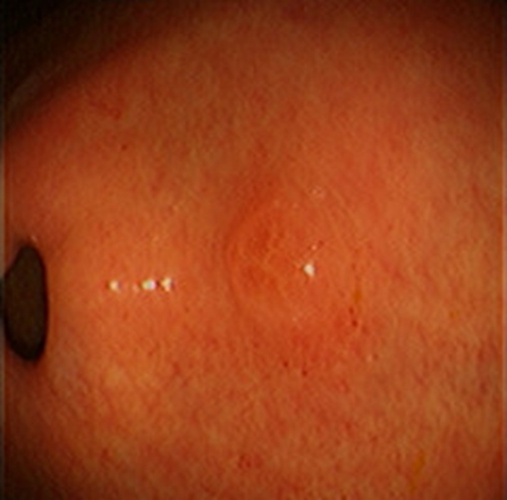

急性胃炎圖片

急性胃炎陽性表現

急性胃炎陽性的表現的

急性胃炎陽性的表現